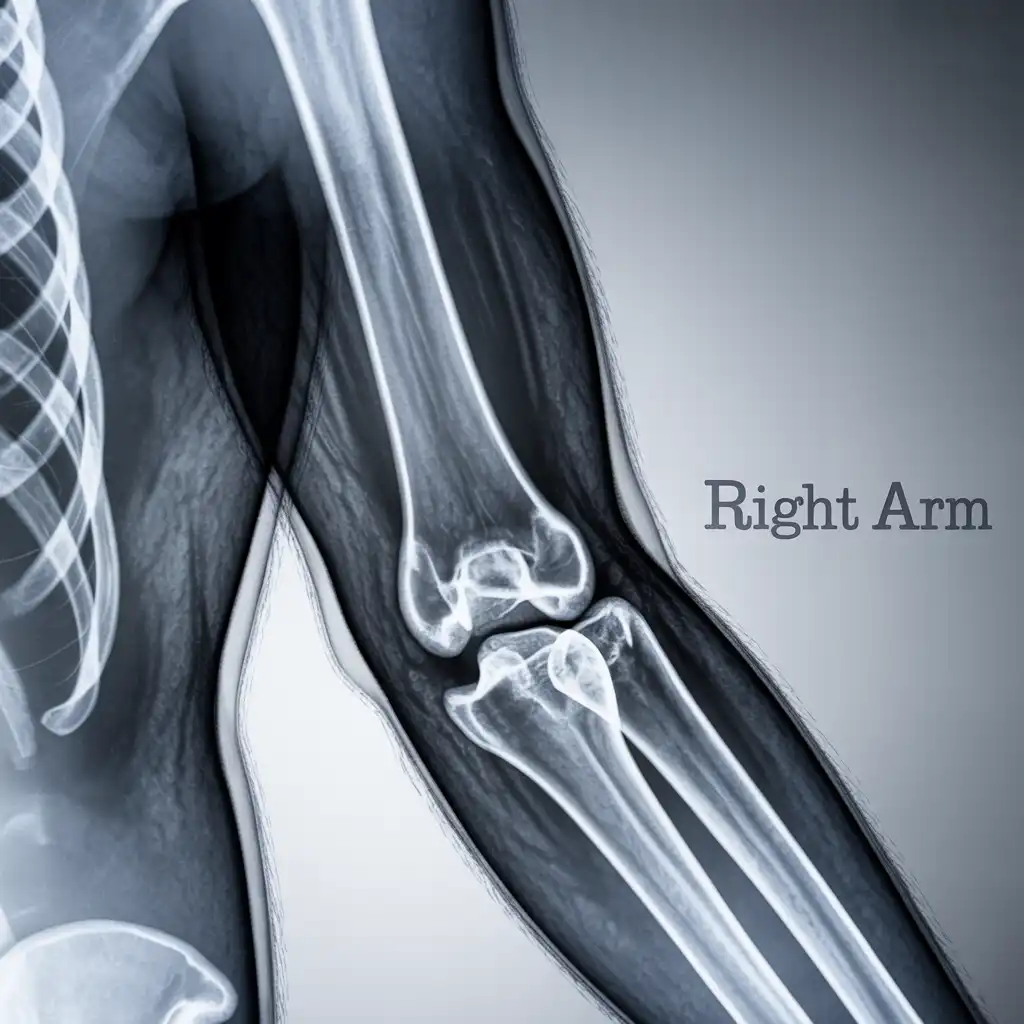

Una lastra a domicilio è una radiografia eseguita direttamente a casa del paziente, grazie all’intervento di un tecnico sanitario qualificato dotato di apparecchiatura digitale portatile.

L’esame viene effettuato sul posto, senza necessità di spostare la persona dal letto o dalla poltrona, e garantisce una qualità diagnostica paragonabile a quella di un reparto ospedaliero.

Una volta acquisite, le immagini vengono trasmesse al medico radiologo, che le analizza e redige il referto in tempi brevi.